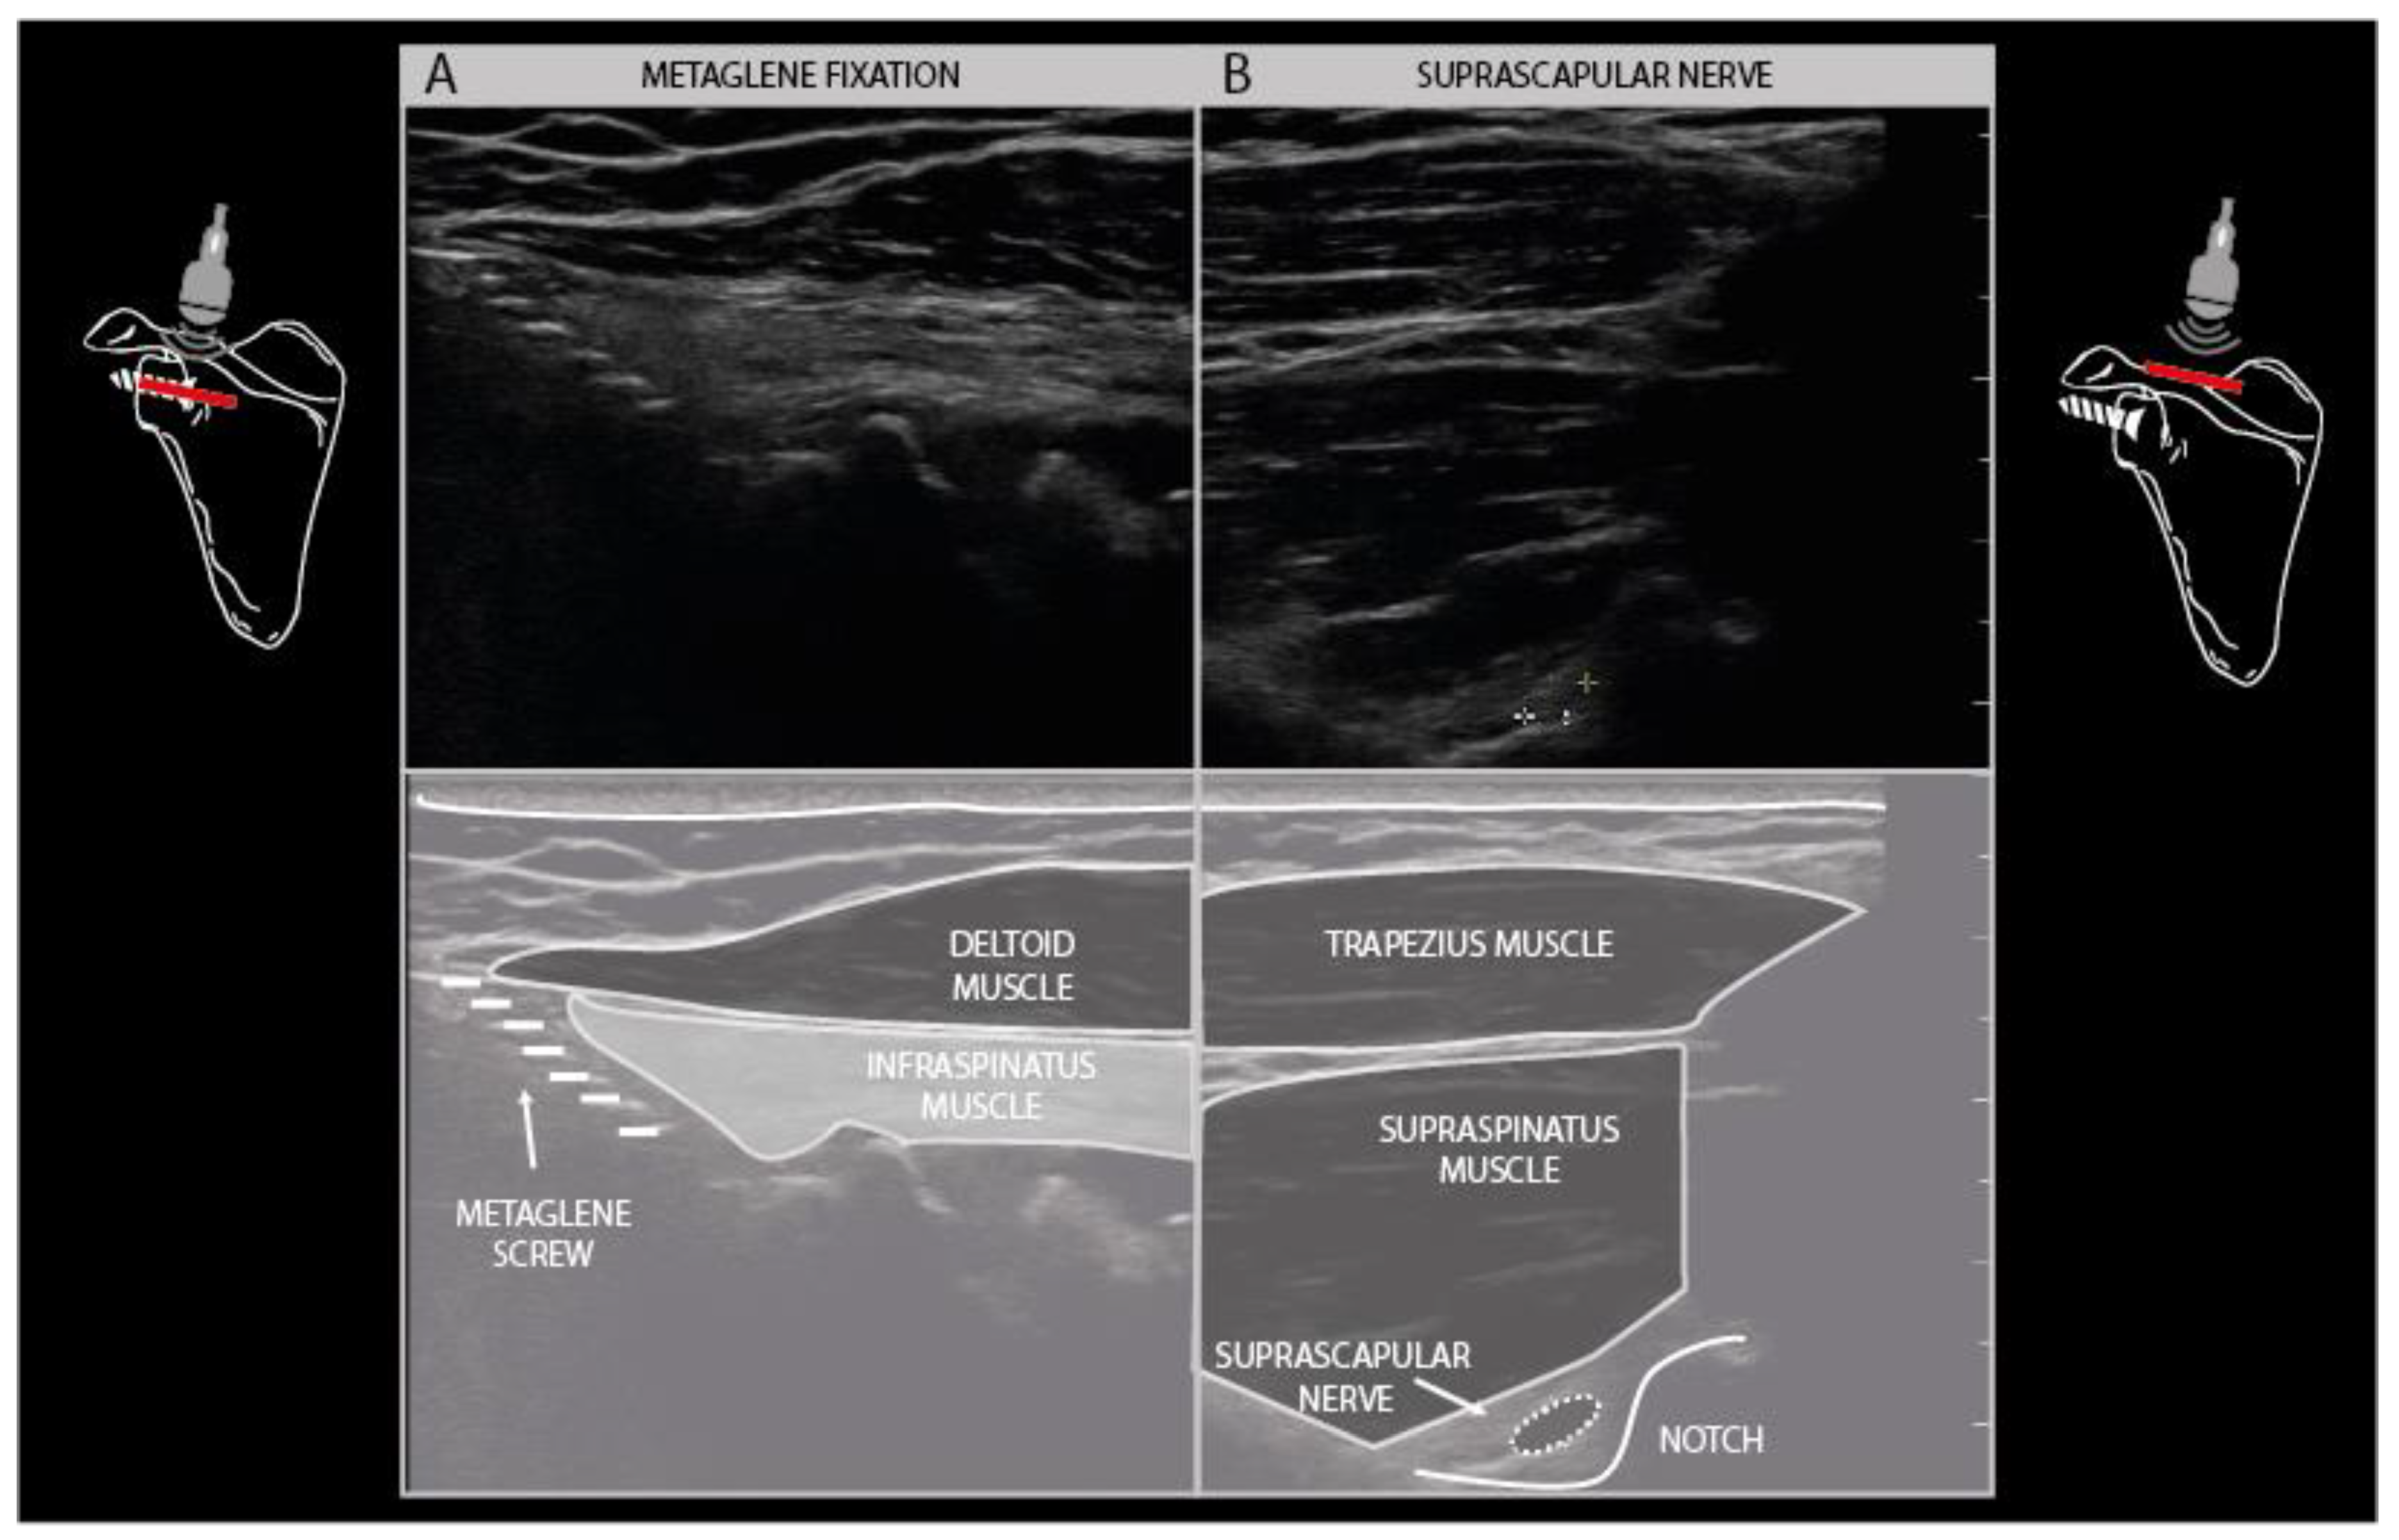

Another common finding is the presence of osteosynthesis material in the vicinity of the injured nerve. Fixation plates and screws and K-wires can usually be visualized with ultrasound as hyperechogenic edges and structures that cover or pierce a bony cortex in the vicinity of the nerve (Figure 7F). It is well known that the placement of osteosynthesis material for certain indications poses a risk to peripheral nerves in that area, such as the radial nerve during humeral shaft fixation, the suprascapular nerve during metaglenoid fixation in reversed total shoulder arthroplasty, and the ulnar nerve during temporary elbow fracture fixation (Figure 13).

Figure 13.

Reverse shoulder arthroplasty with metaglene fixation screw traction injury to the suprascapular nerve. Hyperechogenic, denervated infraspinatus muscle layer underneath a normal appearing deltoid muscle (A). Suprascapular neuroma in continuity (3× normal size) at the level of the spinoglenoid notch (B).